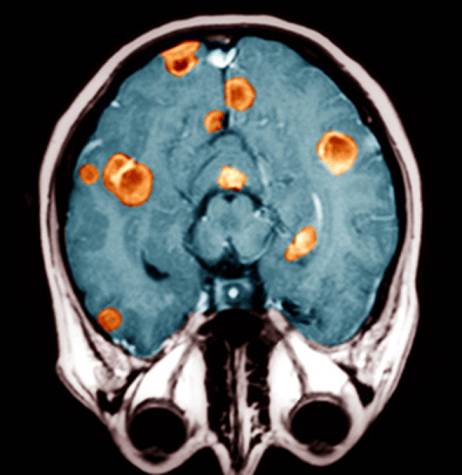

Метастазы в голове диагностируются в 10 раз чаще, чем первичные опухоли мозга. Эта патология довольно тяжело поддается лечению.

По статистике, каждый четвертый пациент с онкологией имеет метастазы в головной мозг.

Метастазы в головном мозге представляют собой тяжелое осложнение, которое может привести к летальному исходу, если не проводить никакого лечения. Метастазы в голове (код по Мкб 10 – С71) являются серьезным осложнением рака.